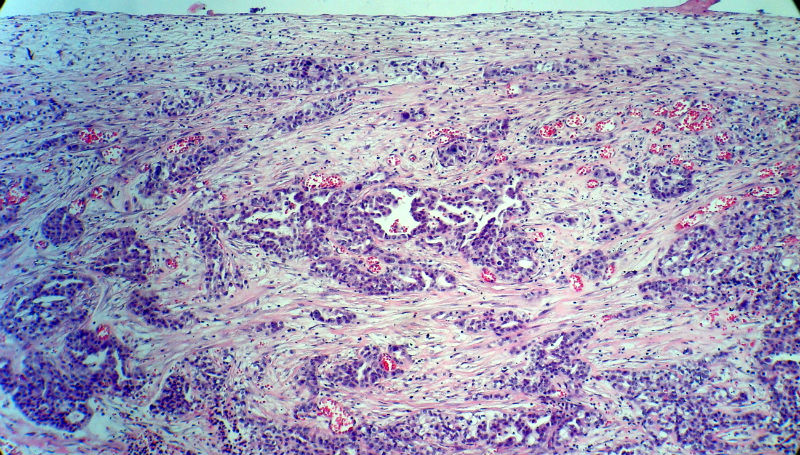

男,82岁,小肠穿孔紧急手术。

大体,小肠一段,长约60厘米,与粘膜面可见三个溃疡型肿物,肠系膜淋巴结肿大。

肿瘤呈巢片状分布,细胞大小相对一致,胞浆丰富,胞核呈细颗粒状,可见小核仁,血管较丰富,考虑神经内分泌肿瘤,加做免疫组化(Ki67、Syn、NSE、CgA、CD56)分级。

神经内分泌肿瘤,加做免疫组化(CKp、Ki67、Syn、NSE、CgA、CD56)分级。